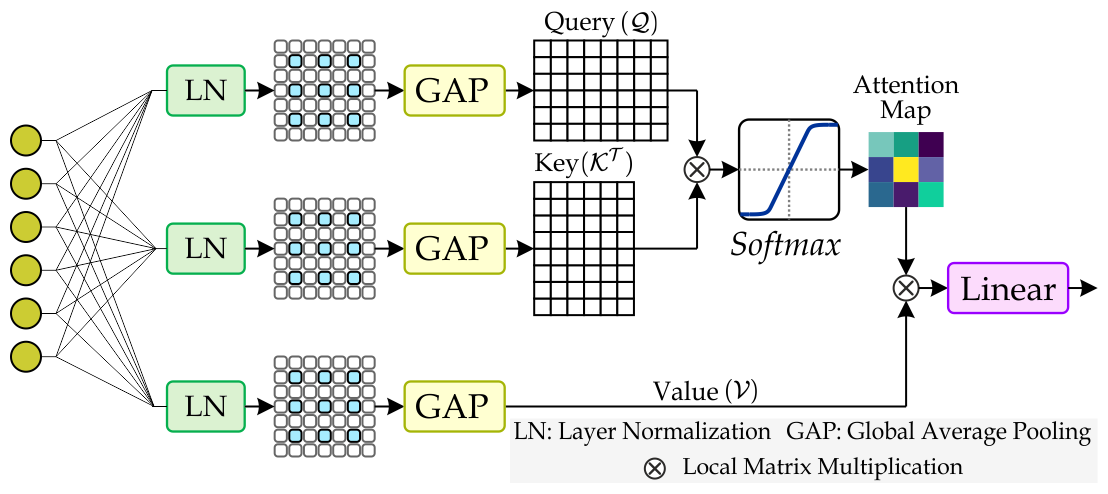

As illustrated in Fig. 2, the Spatial-Enhanced Attention (SEAt) unit, a core component of the HMAtt module, captures spatial-aware global dependencies within the multi-scale aggregated features derived from the MSFA unit. The SEAt comprises a Fully Connected (FC) layer, MHSEAt, feed-forward layers, and a dropout layer. Due to the pivotal role of the attention mechanism within SEAt, we provide a detailed introduction to MHSEAt below.

Multi-Head Spatial-Enhanced Attention (MHSEAt): The Multi-Head Spatial-Enhanced Attention (MHSEAt) performs the self-attention operation along the spatial dimension. As shown in Fig. 4, firstly, the three identical copies of feature maps are normalized through Layer Normalization , followed by convolution operation with kernel having dilation rate of . Next, the spatial-enhanced features are aggregated with Global Average Pooling to obtain the Query (), Key (), and Values (). We can formulate the process mentioned above as follows:

| (5a) |

| (5b) |

| (5c) |

| (6) |

Here, is the input feature map, are the projection matrices, denotes the softmax function, denotes the dimension of the key and is the feature map after linear spatial reduction multi-head spatial-enhanced attention.

The SEAt unit follows the MHSEAt layer with two stacked Fully Connected (FC) layers. Each layer uses the ReLU activation (denoted by ) to incorporate non-linearity, allowing the network to model complex data relationships. Formally, , where represents the spatial-enhanced attention features. This process effectively captures local and global dependencies while preserving spatial information in the final output, .

Table 5 summarizes the segmentation performance of the proposed MNet-SAt, which incorporates Layer Normalization (LN), a dilation rate of 2, and Global Average Pooling (GAP). In comparison to the variant without LN and a dilation rate of 1, the performance of the proposed MNet-SAt significantly improves, with an increase of 2.35% and 3.41% in DSC and IoU. Incorporating LN and increasing the dilation rate to two improves performance to 95.87% and 95.79% in DSC and IoU. Furthermore, including Global Average Pooling (GAP) within SEAt maintains spatial invariance and leads to further performance gains. These results underscore the role of the spatial enhanced attention module in improving polyp segmentation performance.

| Methods | DSC|∇| | IoU|∇| | Pre|∇| | Rec|∇| |

| MNet-SAt | 94.26 | 93.51 | 94.17 | 94.12 |

| MNet-SAt | 95.87 | 95.79 | 95.38 | 96.10 |

| MNet-SAt | 96.61 | 96.92 | 97.36 | 97.12 |

| LN: Layer Normalization, : dilation rate, GAP: Global Average Pooling | ||||